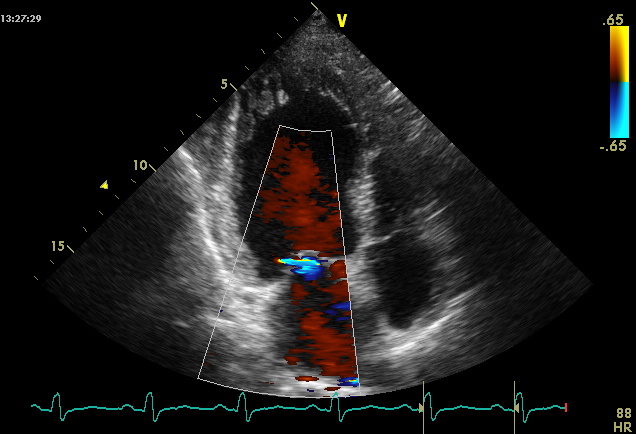

Эта патология может быть как наследственной, так и приобретенной. Для ее отличия от аортального стеноза, гипертензии и коарктации аорты важно отметить отсутствие постнагрузки на миокард желудочков. При проведении эхокардиографии наличие систолических шумов указывает на обструктивный тип гипертрофической кардиомиопатии.

- эхокардиографию;

При тяжелых формах кардиомиопатии врачи могут дополнительно назначить половые гормоны, если пациент достиг 14 лет. Для контроля эффективности лечения необходимо регулярно проходить обследования. Основные методы диагностики в этом случае — ЭКГ и ЭхоКГ, которые позволяют выявить даже незначительные изменения в размерах желудочков. О выздоровлении свидетельствует снижение болевых ощущений в покое и при физической активности.